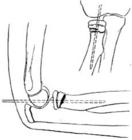

取兩塊長短適當的木板(由肘至手心),墊以柔軟襯物,將兩塊夾板分別放在前臂掌側與背側(只有一塊夾板時放在前臂背側),並在手心放棉花等柔軟物,讓傷員握住,使腕節稍向背屈,然後,上下兩端扎牢固定,再屈肘90度,用大懸臂帶吊起。

②衣襟、軀幹固定:

利用傷員身穿的上衣固定。將傷臂屈曲貼於胸前,把手放在第三、四鈕扣間的前衣襟內,再將傷側衣襟向外翻,反折上提,托起前臂衣襟角系帶,拉到健肢肩上,繞到傷肢肩前與上衣的衣襟打結。無帶時可在衣襟角剪一小孔,掛在第一、二鈕扣上,再用腰帶或三角巾經肘關節上方繞胸部一周打結固定。